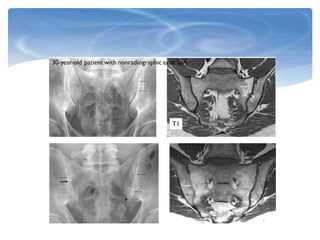

Sacroiliitis

0 Normal

1 Some blurring of the joint margins - suspicious

2 Minimal sclerosis with some erosions

3

Severe erosions with widening of joint space +/- some ankylosis

(Pseudo-widening of the joint space: Subchondral bone resorption—

blurring ; Erosion sclerosis ;Calcification leading to ankylosis)

4 complete ankylosis

Grade 0 Grade 1 Grade 3 Grade 4

20歲年輕女性,

HLAB27+

相隔四年的X光片